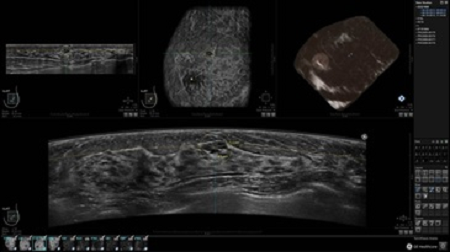

• Получение объемных 3D изображений с возможностью покадрового просмотра

• Получение изображений в поперечной плоскости (в реальном времени) и в коронарной плоскости (статическая, для указания нахождения соска)

Технические параметры рабочей станции

• Отображение объемных 3D ультразвуковых изображений, которые состоят из традиционных поперечных и воссозданных коронарных и сагиттальных проекций

• Возможность отображения полного 3D изображения

• Стандартизованная ориентация изображения: «толстый срез» в коронарной плоскости; поперечная; сагиттальная плоскость; радиальный и антирадиальный поворот изображения; просмотр исключительно области интереса

• Изменяемая толщина среза: 0,5 - 10,0 мм (шаг 0,5 мм)

• Срез: 0,5 - 2,0 мм (шаг 0,5 мм)